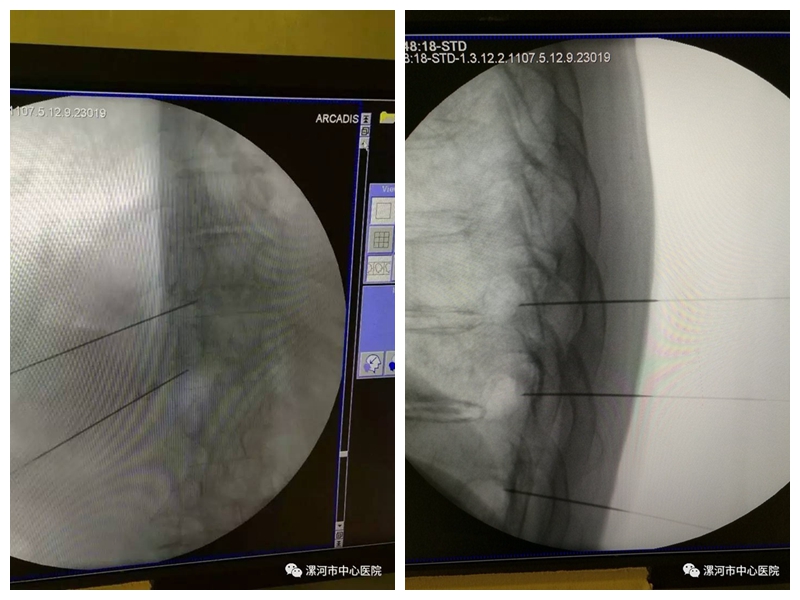

在无菌手术室中,疼痛科副主任汪庆玎在C型臂X线持续监视下,将长15CM的射频套管针经患者背部穿刺定位到胸椎椎间孔后,植入刺激电极,以不同频率的电流刺激以分辨感觉与运动根,将刺激电极精确调整到胸神经背根神经节,以脉冲射频电流对神经进行神经调控治疗,4分钟后治疗结束,患者的疼痛就有了明显的缓解,第二天,困扰患者一年的剧烈疼痛消失了。